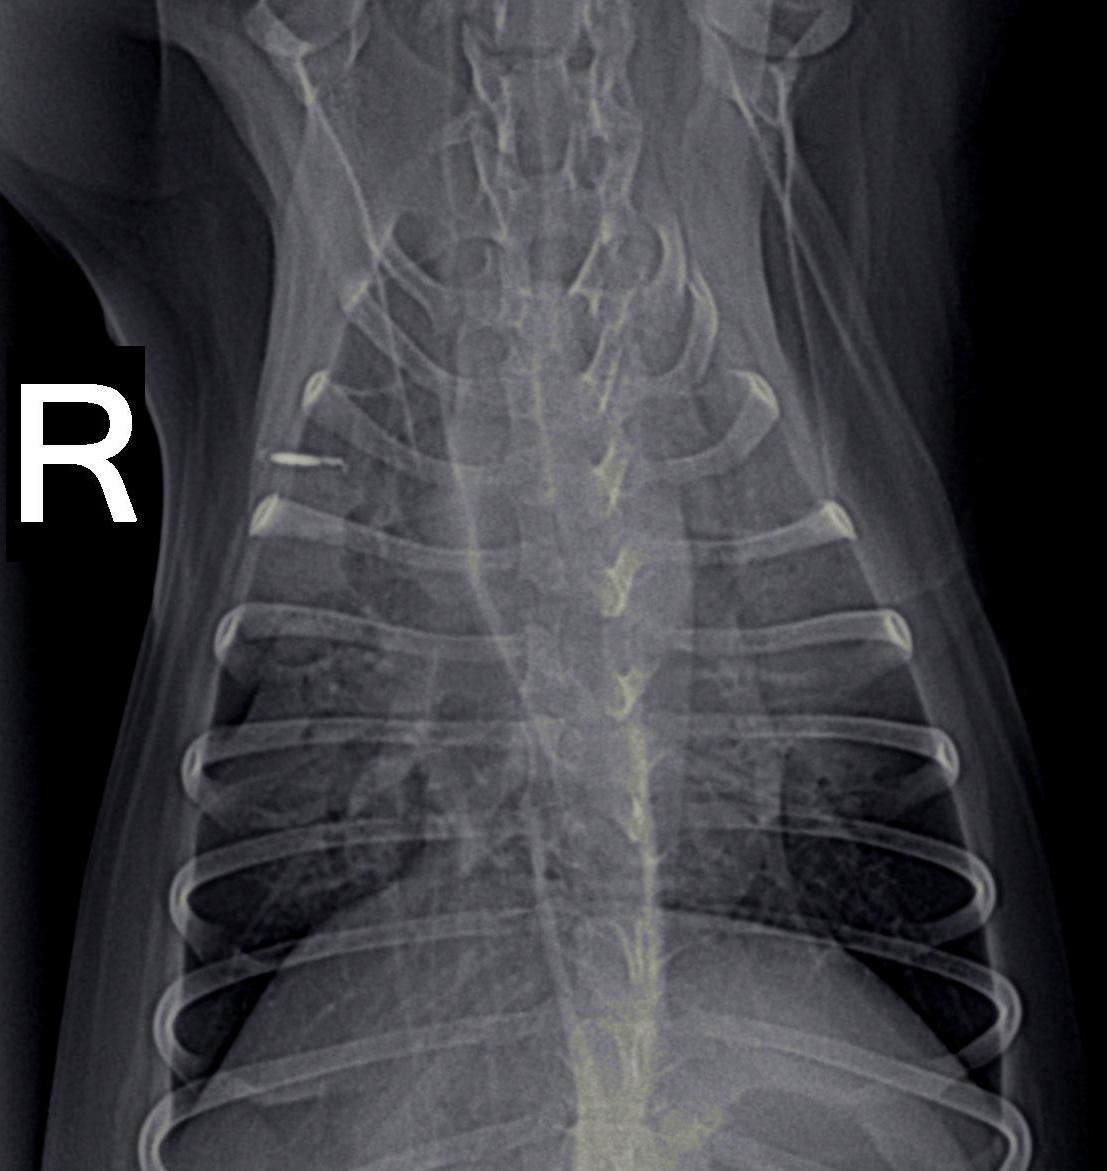

Dogs with tick paralysis may present with an atypical history of vomiting or regurgitation and no apparent neuromuscular weakness (Campbell and Atwell, 2001) (Malik et al., 1988). Careful veterinary diagnostic evaluation to exclude other causes of vomiting is essential along with coat clipping combined with regular and repeated whole-body searches for ticks. Evidence of megaoesophagus (Figures 7, 8), defined as oesophageal dilation on radiographs, was found in 70% (28/40) of dogs diagnosed with tick paralysis (Campbell and Atwell, 2001). In another study utilising only a single left lateral chest xray at admission, 19% of dogs had radiographic evidence of megaoesophagus (Day and Schull, 2008). The development of megaoesophagus was not significantly associated with the tick location being on the neck or throat region. Megaoesophagus was more likely to be detected in older dogs with tick paralysis and recovery of oesophageal function lagged behind that of generalised tick paralysis (Campbell and Atwell, 2001). Vomiting and regurgitation without classical signs of paralysis has been described and a series of three such case presentations has been described (Malik et al., 1988). The extreme difficulty in obtaining a diagnosis was highlighted in this report. Multiple days hospitalisation elapsed before diagnosis of tick paralysis, death of two of the dogs, and exploratory laparotomy surgery performed in one case in an attempt to diagnose the cause of the gastrointestinal upset which later died (Malik et al., 1988). None of the three dogs were reported to have displayed signs of generalised paralysis demonstrating the difficulty veterinarians face with atypical tick paralysis cases.

The frequency of megaoesophagus in dogs with tick paralysis and the radiographic visibility on plain views of this condition would suggest that its identification may be a useful diagnostic screening test in suspect cases. Thoracic radiographs could be used to support administration of TAS in cases where no tick can be found.